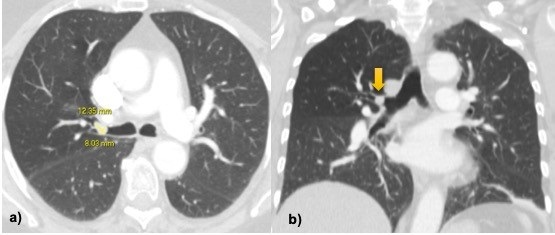

CT evaluation played a major role in the detection of a 12 x 8mm, rounded lesion, with soft-tissue attenuation (mean of 55 Hounsfield units) of the right main bronchus. The right upper lobe had no atelectasis or consolidation. There was a subtle decrease in the lung density in this lobe likely related to partial compression of the airway and subsequent reduced ventilation. The CT acquisition was repeated after cough maneuver for differential diagnosis with dense mucous plugging, and no change was noticed in the position or shape.

Figure 1: a, b) Axial and coronal images CT show a 12x8mm soft-tissue nodule inside the right main bronchus. There is slight reduction in the density of right upper lobe likely related to decreased pulmonary ventilation but no atelectasis nor consolidations is seen.